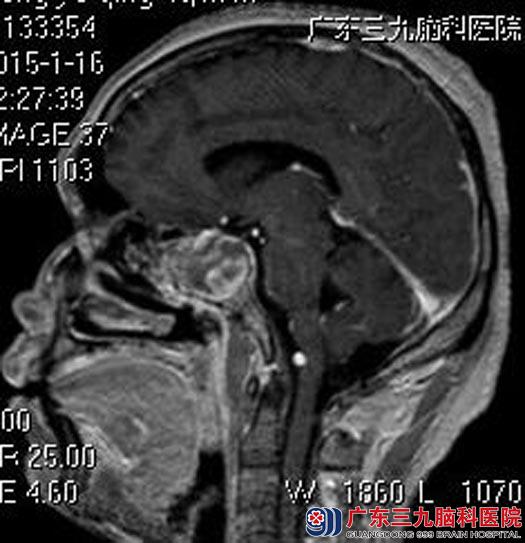

汤先生来到广东三九脑科医院垂体瘤诊疗中心时已双侧瞳孔不等大,左侧瞳孔直径约4mm,对光反射迟钝,右侧瞳孔直径3mm,双眼视野及右眼上、下视野缺失。广东三九脑科医院头颅MR检查提示:鞍区示一不规则形占位性病变,大小约29.9mm×32.5mm×38.7mm,考虑垂体大腺瘤合并肿瘤卒中。

手术前